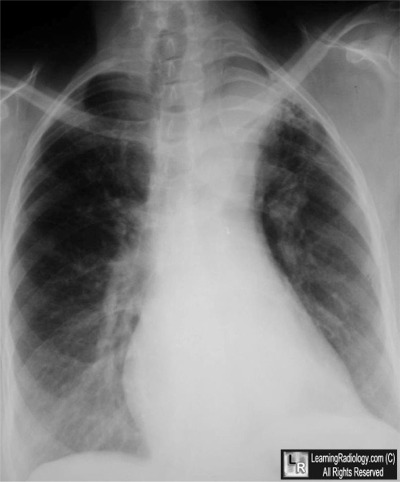

Additional Image-Frontal Chest Radiograph

Frontal Chest Radiograph

5. Cervical Aortic Arch

Cervical Aortic Arch

• Rare congenital anomaly

• Usually defined as a supraclavicular position of the aortic arch

• More common on the right side

• 2:1 female:male predominance

47 year-old with pulsatile left supraclavicular mass